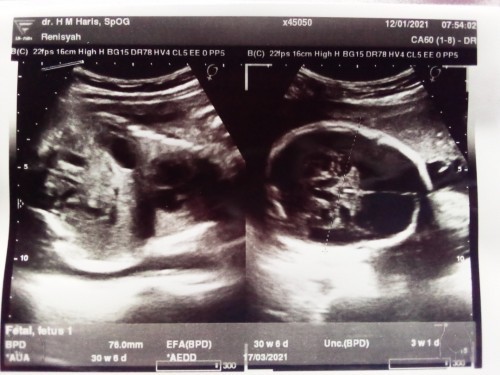

Bun aku mau cerita nih, kan pas pertama kali di periksa ke Tante bidan pasti di tanya kapan terakhir haidnya kan nah disitu aku jawab tanggal 8 Juli 2020 dong tapi kenapa Tante bidanya nulis di buku KIA nya tanggal 10 Juni 2020 kan waktu bulan Juni aku masih haid lancar masa iya di itung juga🙄, trus hpl Tante bidan tanggal 17 bulan Maret 2020 usia kehamilan aku udah 7 bulan dong ya, aku blum USG sama sekali ya Bun dari awal kehamilan kata suami ntr aja nunggu sebulan lagi baru USG ywdh aku nurut aja, buat bunda" yang lainya ada yang sama Kya aku ga?#seriusnanya #bantusharing #jangandibully